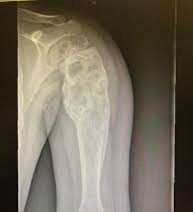

Se usa una amplia gama de técnicas de adquisición de imágenes para poder ver dentro del cuerpo y determinar el alcance de un sarcoma óseo y establecer la presencia o ausencia de enfermedad metastásica distante.

1. Rayos X

2. Resonancia magnética

3. TAC contrastado

4. Gammagrafía Ósea